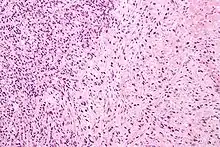

Gleason pattern 4. H&E stain.

Gleason pattern 4 (left of image) and Gleason pattern 5 (right of image). H&E stain.

• Pattern 4 - The tissue has few recognizable glands. Many cells are invading the surrounding tissue in neoplastic clumps. This corresponds to a poorly differentiated carcinoma.

• Pattern 5 - The tissue does not have any or only a few recognizable glands. There are often just sheets of cells throughout the surrounding tissue. This corresponds to an anaplastic carcinoma.

Gleason 4

Gleason pattern 4 glands are no longer single/separated glands like those seen in patterns 1-3. They look fused together, difficult to distinguish, with rare lumen formation vs Gleason 1-3 which usually all have open lumens (spaces) within the glands, or can be cribriform-(resembling the cribriform plate/similar to a sieve: an item with many perforations). Fused glands are chains, nests, or groups of glands that are no longer entirely separated by stroma-(connective tissue that normally separates individual glands in this case). Fused glands contain occasional stroma giving the appearance of "partial" separation of the glands. Due to this partial separation, fused glands sometimes have a scalloped (think looking at a slice of bread with bite taken out of it) appearance at their edges.[4][7]

Gleason 5

Neoplasms have no glandular differentiation (thus not resembling normal prostate tissue at all). It is composed of sheets (groups of cells almost planar in appearance (like the top of a box), solid cords (group of cells in a rope like fashion running through other tissue/cell patterns seen), or individual cells. You should not see round glands with lumenal spaces that can be seen in the other types that resemble more the normal prostate gland appearance.[4][7]